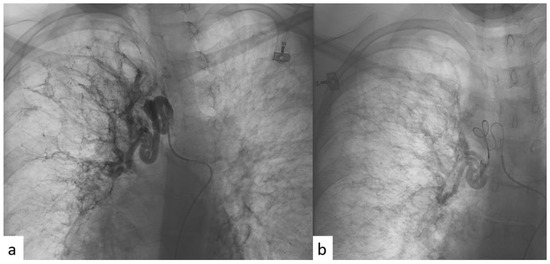

2.3. BAE Procedure